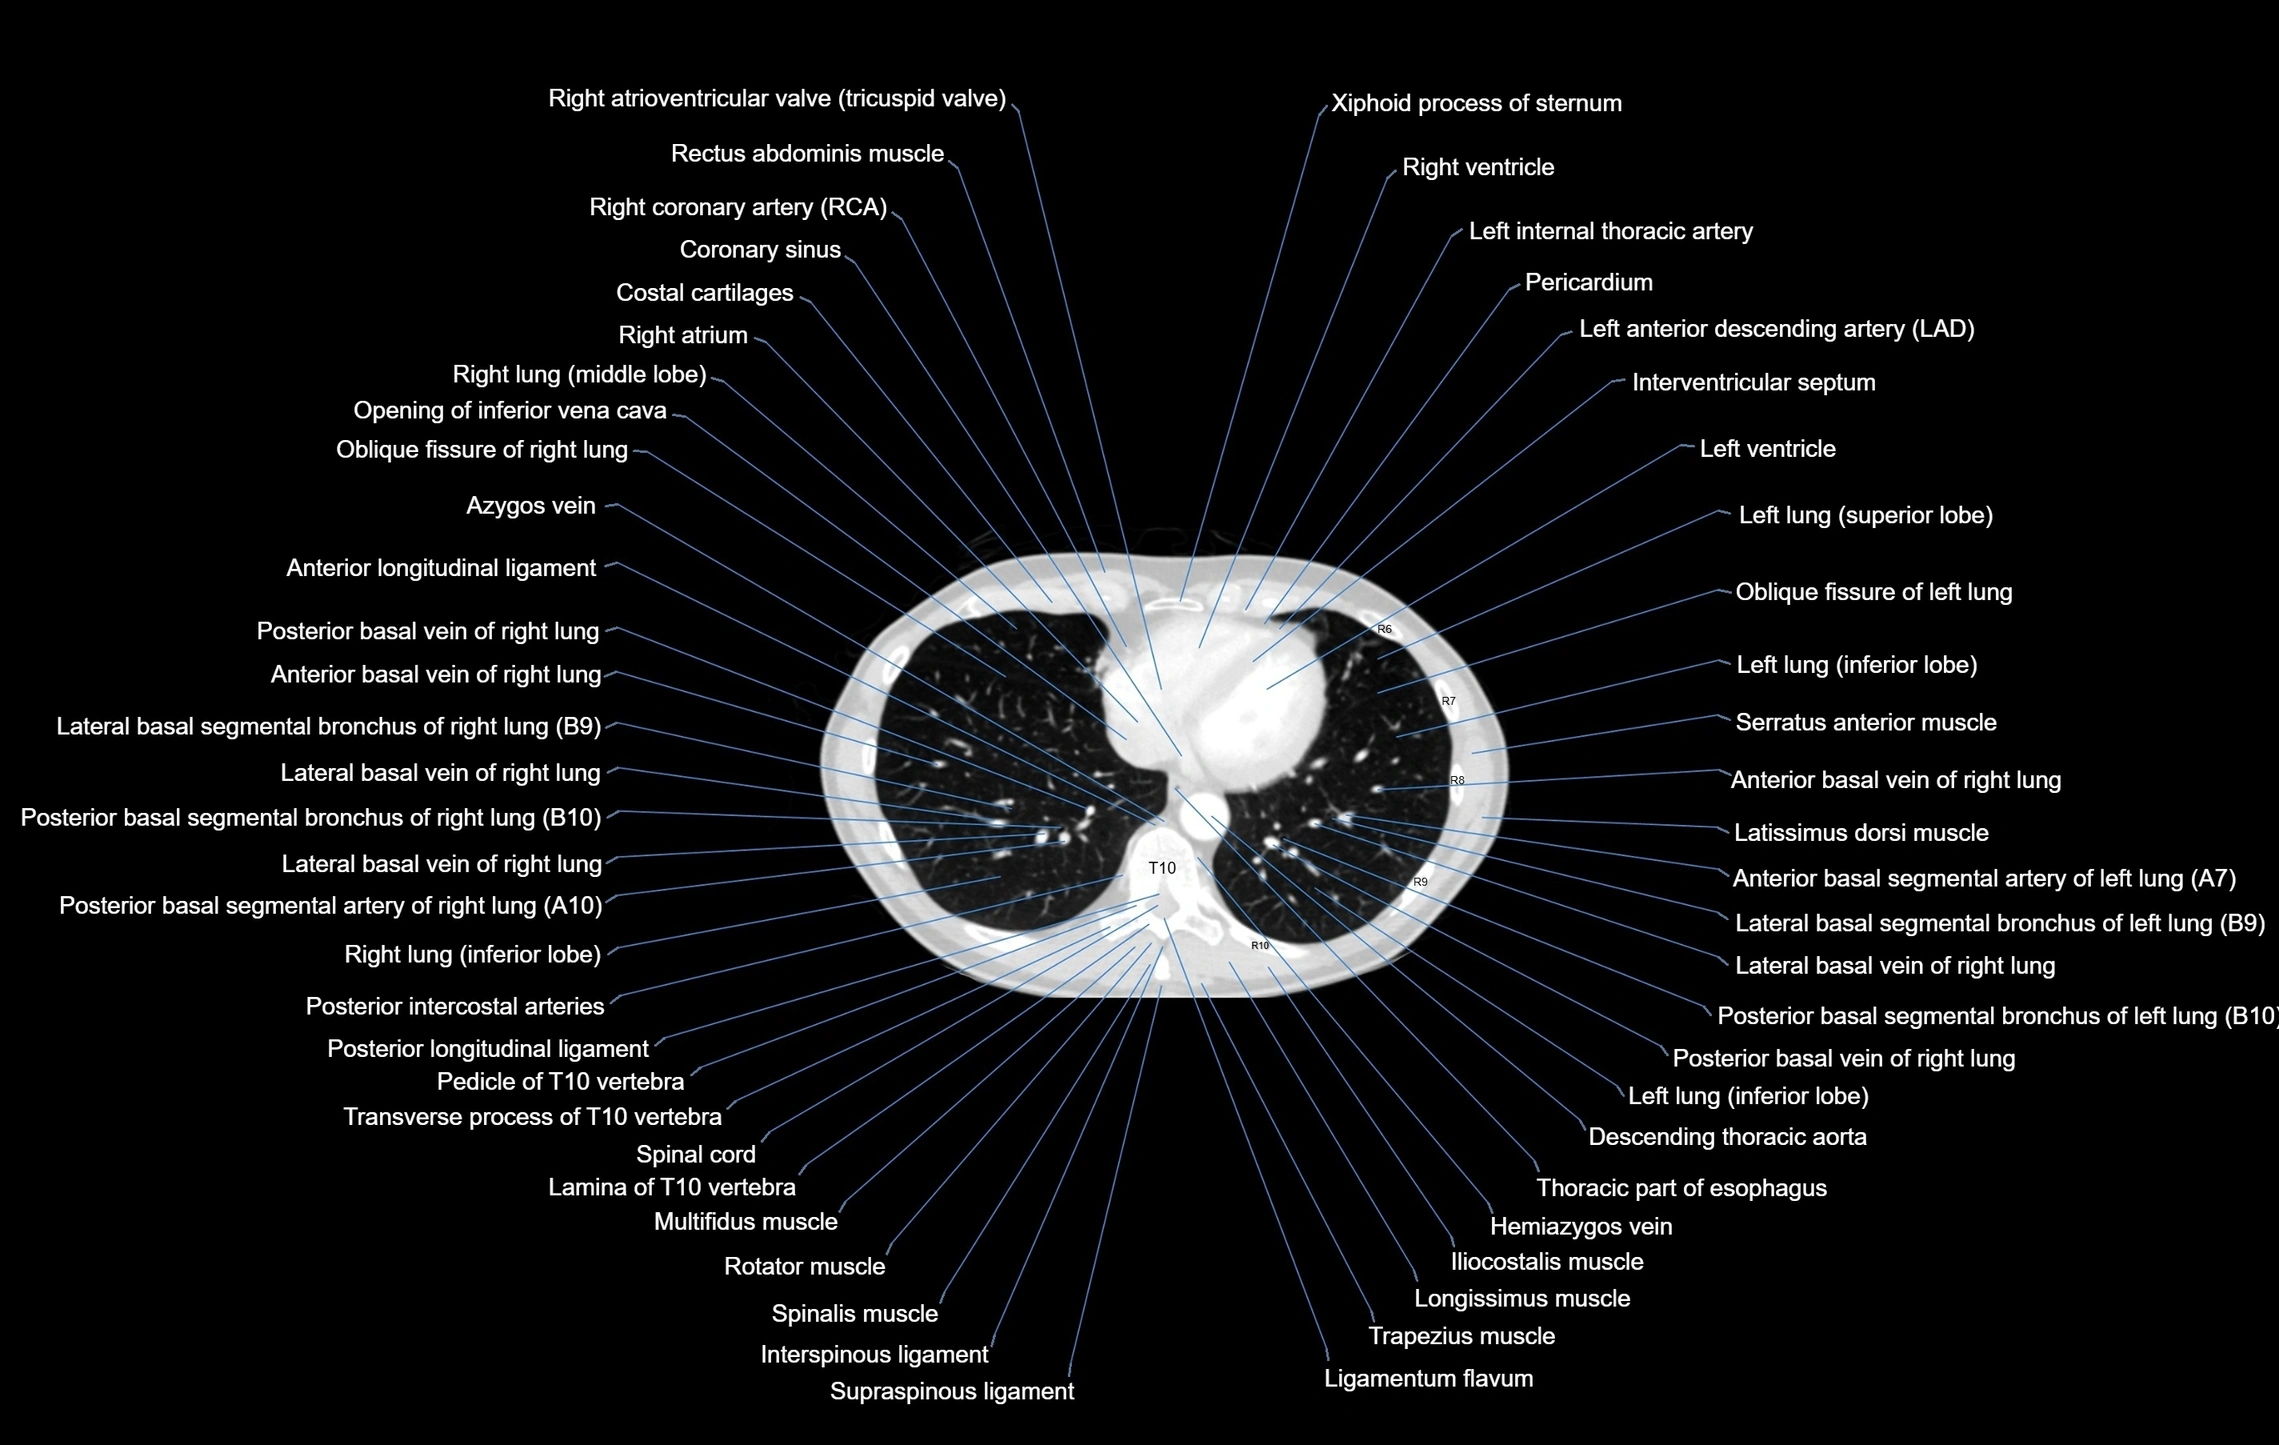

- T (Thoracic spine)